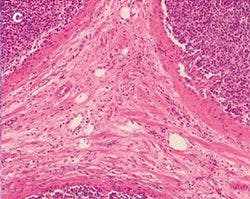

The practical effect of the color shift caused by a generic LED light source, both with and without a CC filter, is clearly visible when imaging a stained tissue section using the different light sources. Figure 5 shows a tissue section illuminated by the three different light sources mentioned before.

Figure 5: Stained Tissue Section a

Figure 5: Stained Tissue Section

Differences between halogen lamp (a) and LED illumination (b) lead to tissue stainings shifting to blue, both through the oculars and on the screen. Adding a CC filter (c) mitigates the issue, but still gives a yellowish appearance.